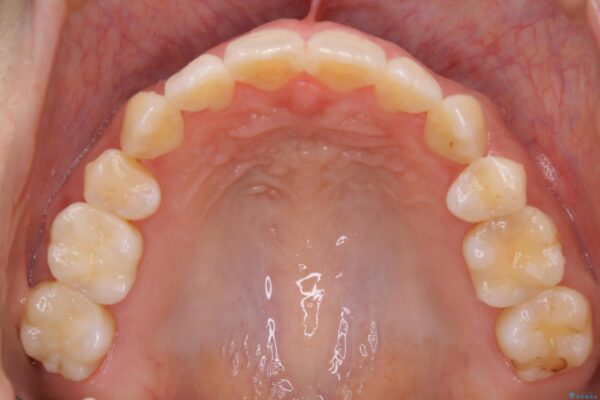

30代 女性 インビザラインで抜歯矯正

- 30代女性

- 2年6ヶ月

- 104.5万円(インビザライン コンプリヘンシブパッケージ + マイクロインプラント費用)

来院動機

前歯のガタつき、噛み合わせの不調を改善したいとご来院されました。

治療計画

お仕事柄、目立たない矯正装置をご希望されたため、今回はインビザラインと抜歯を組み合わせた治療で対応します。

抜歯後の大きなスペースの管理は通常ワイヤー矯正が得意ですが、こちらの患者様は奥歯の噛み合わせが比較的安定しており、犬歯の傾きを改善すれば良いため、マウスピースでも十分に精密な治療が可能と判断しました。